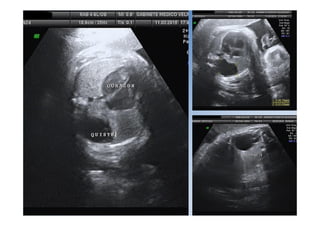

Quiste aracnoideo

• 18.

• 19.

• 20.

• 21.

• Asimetría ventricular• Cisura de Silvio